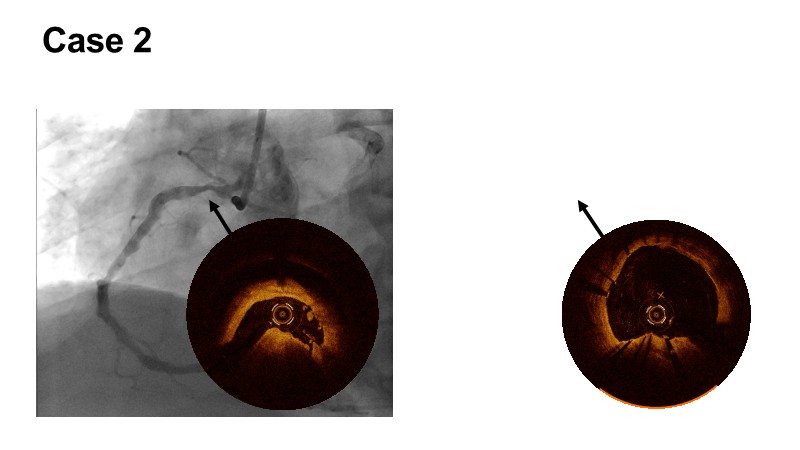

This EuroPCR 2025 session shares real-world insights confirming the promising results of the PINNACLE I trial, with LithiX IVL proving safe and effective across eccentric, concentric, and nodular calcifications.

Learn how this technology works, review the supporting evidence, and follow step-by-step case examples demonstrating optimal stent expansion and an efficient calcium modification workflow in daily practice.